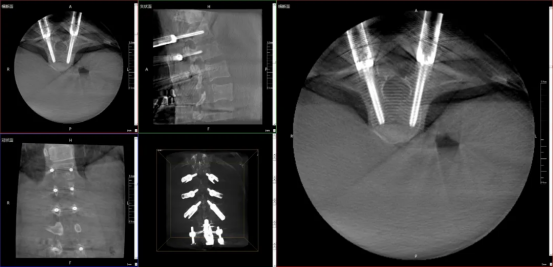

01 Fluoroscopic Vision: Intraoperative 3D Imaging

The device provides full-field 3D images during surgery, helping doctors to assess screw implantation angles and fracture reduction accuracy in real time. It acts like a "fluoroscopic vision" for surgeons, making intraoperative procedures more precise and efficient.

03 Safer: Less Radiation, More Care

The equipment utilizes multiple technologies such as intelligent variable-frequency pulse technology, human graphic interface for preset parameters, and DAP monitoring to strictly control overall radiation exposure, bringing comfort to doctors and patients during prolonged surgeries, transforming clinical precision into compassionate care.